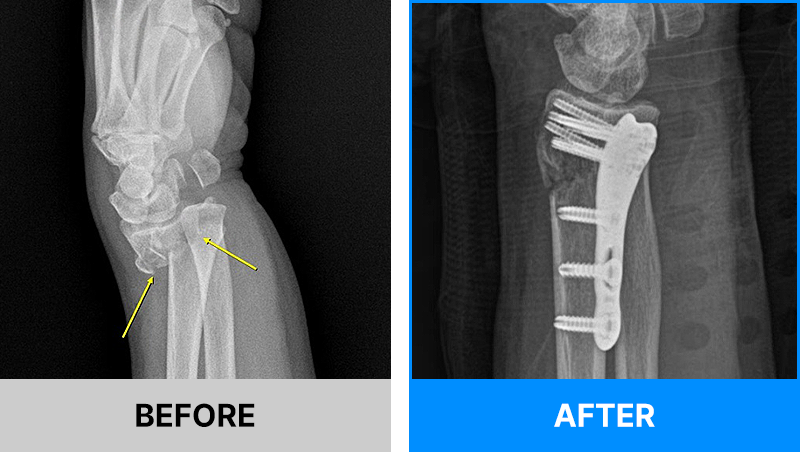

왜 당일 입퇴원 수술일까요?

오래 입원할 필요가 없기 때문입니다.

서울거탑정형외과에서는 전신마취, 척추마취가 아닌

국소부분마취(신경차단) 및 수면 마취를 통해 수술을 시행합니다.

수술 가능 여부 확인은 대표원장과의 진료가 필요합니다.